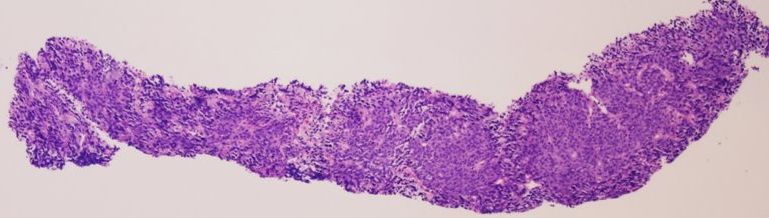

Biopsy (initial findings)

• Large atypical cells

• Negative for CD20

• Negative for CD3

CT-guided Core Needle Biopsy of Abdominal Mass​

What do you make of the biopsy and immunoperoxidase findings?

Interpretation

Loss of lineage markers creates diagnostic uncertainty.

CD20 negativity does not exclude B-cell lymphoma

→ may occur after prior therapy or in aggressive disease

Additional studies

• PAX5 positive

• Ki-67 high

• CD23 negative

What do these findings indicate?

a

High-grade B-cell lymphoma

PAX5 confirms B-cell lineage despite loss of surface markers. High Ki-67 indicates aggressive proliferation. Loss of CD23 (typically present in CLL) supports transformation to a different phenotype